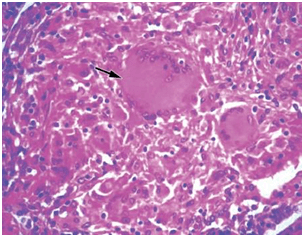

间质性肺炎切片

间质性肺炎病理切片